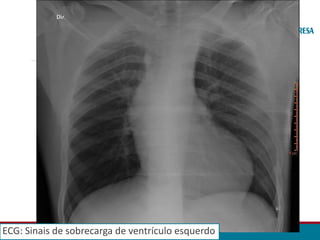

• Ao realizar exames de rotina, o Eletrocardiograma evidenciou sinais

de sobrecarga do ventrículo esquerdo.

ECG: Sinais de sobrecarga de ventrículo esquerdo